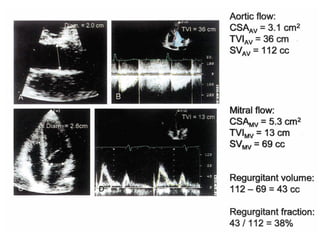

STROKE VOLUME AT MITRAL ANNULUS

STROKE VOLUME ATMITRAL ANNULUS